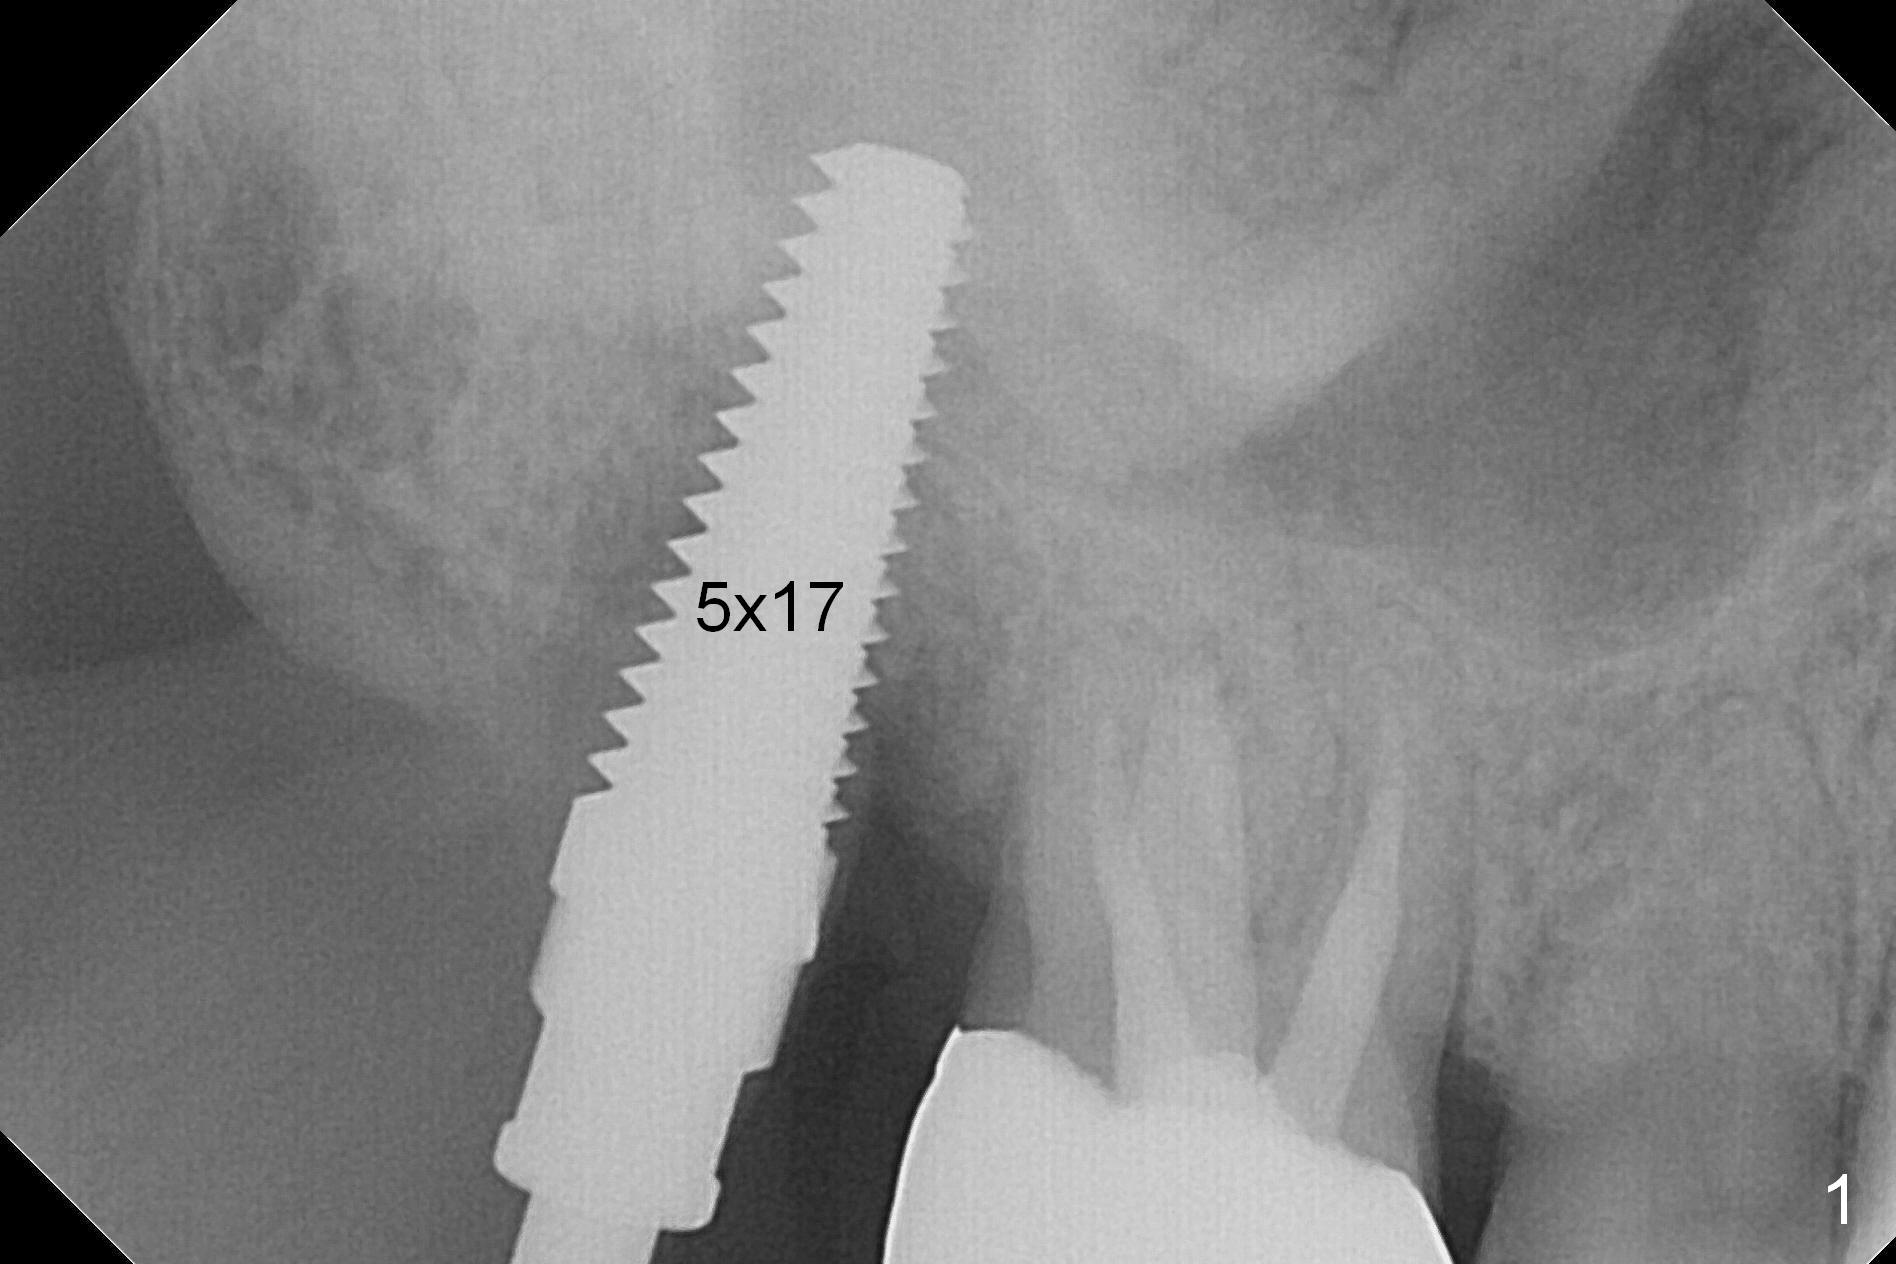

The tooth #2 is found to have fracture at extraction.  The buccal (B) socket (*) has more resorption than the palatal (P) one (Fig. A (S: sinus).  The buccal plate is also lower.  Osteotomy is initiated in the buccal slope of the septum with Magic Expanders (ME, 3-4.8 mm, Fig. B (red)), followed by Tatum tapered tap drills (Fig. C (green), Fig.1 (5x17 mm)).  As the diameter of ME and tap increases, the osteotomy is shifting buccally due to bone height discrepancy (Fig. C).  A Lindamann bur is used to remove the palatal bone (Fig. D (pink) and move the osteotomy palatally (Fig. E).  The coronal end of 7x14 mm tissue-level fixture (Fig.2) tilts buccally (Fig. F purple).  Insertion torque is 35/40 Ncm.  Prior to implantation, a piece of PRF membrane and allograft are pushed into the sinus.  A 6x3 mm abutment (Fig.2) is immediately placed to keep an immediate provisional, bone graft and collagen membrane in place.  Bone seems to have grown into the space between the implant threads 5.5 months postop (Fig.3).  There is no bone loss 2 years 2 months post cementation (Fig.4).